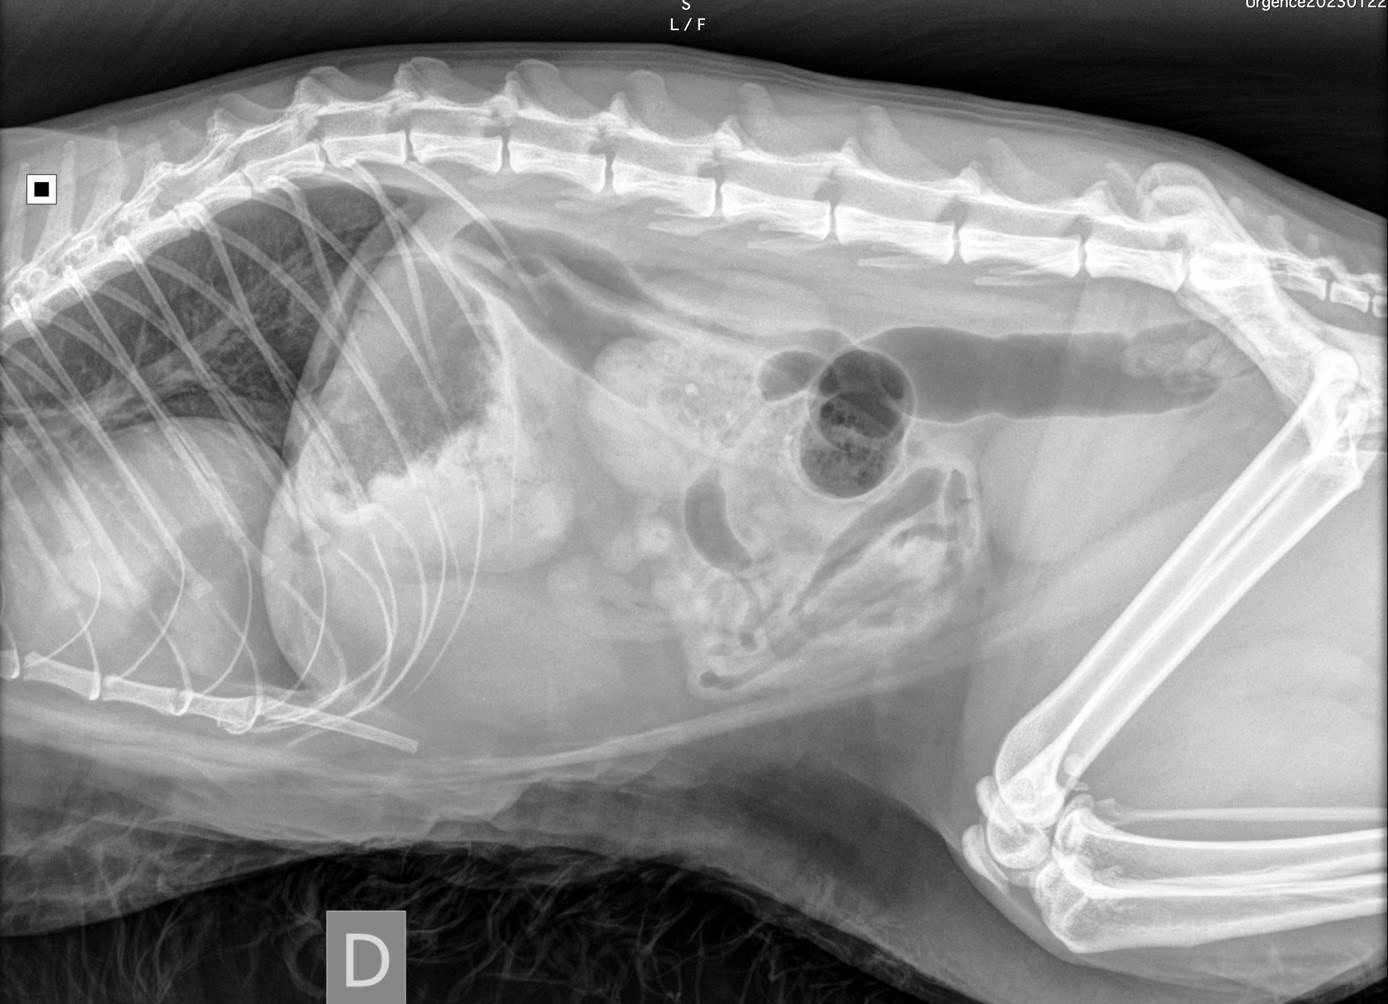

Un chat de 8 ans est présenté pour vomissements évoluant depuis trois jours. À l’examen clinique, le chat présente une palpation abdominale douloureuse. Des radiographies abdominales (photo 1) puis thoraciques (photos 2a et 2b) sont réalisées.

Photo 1 : projection latérale droite de l’abdomen montrant une lésion thoracique

On note un élargissement de la silhouette cardiaque d’opacité hétérogène graisseuse et tissulaire (flèches). Les contours du foie ne sont pas visibles dans l’abdomen cranial avec déviation craniale de l’axe gastrique (ligne bleue).

En conclusion, on observe une cardiomégalie d’opacité hétérogène associée à une malposition des organes abdominaux, notamment du foie.

Photo 3 : projection latérale droite de l’abdomen montrant l’opacité hétérogène de la silhouette cardiaque et la déviation craniale de l’axe gastrique